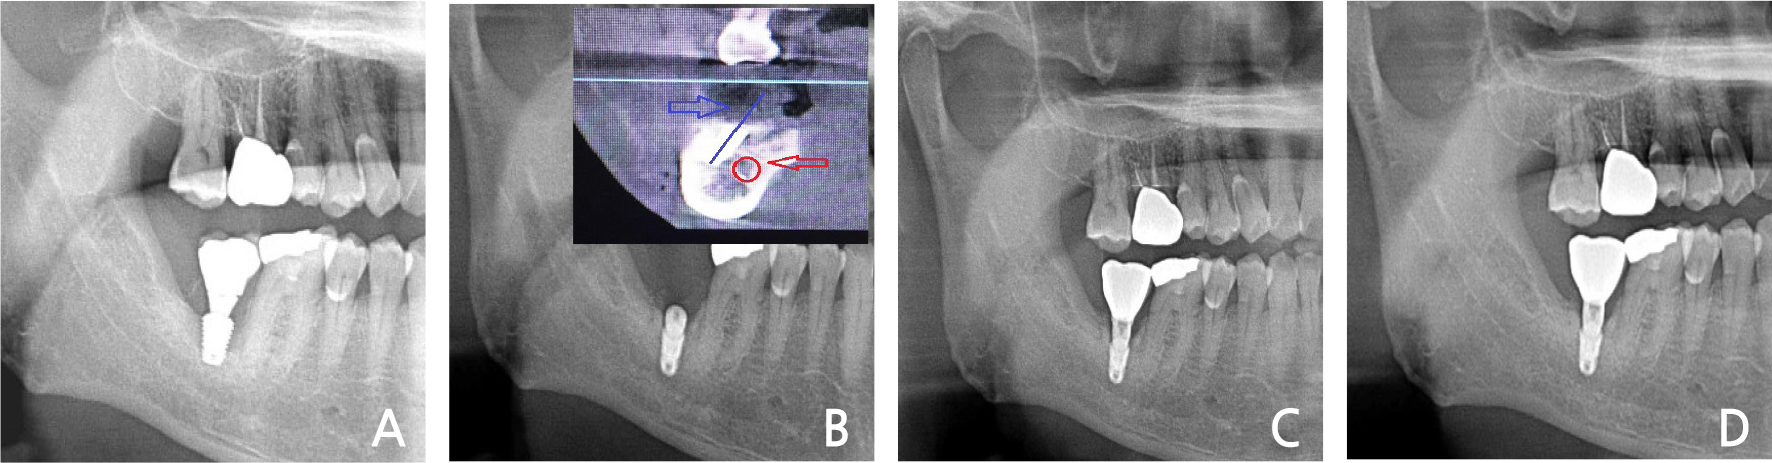

A 55-year-old man presented with severe pain in the left maxillary 2nd molar.

Clinical and radiological evaluation revealed severe mobility of the left maxillary 2nd molar and a cystic lesion in the crown area of the left maxillary 3rd molar (Fig. 1A). Spontaneous bleeding, purulent exudate, and periodontal abscesses were observed. He had no history of systemic disease. Under local anesthesia, a three-sided flap was elevated and the 2nd molar & 3rd molars were extracted. The cystic lesion was removed and immediate implant placement with sinus elevation (lateral approach) was performed (Fig. 1B). The primary anchorage was provided by the inferior wall of the sinus. After two months, loading was performed (Fig. 1C). In the 3-years follow-up, the bone & implant was intact (Fig. 1D).